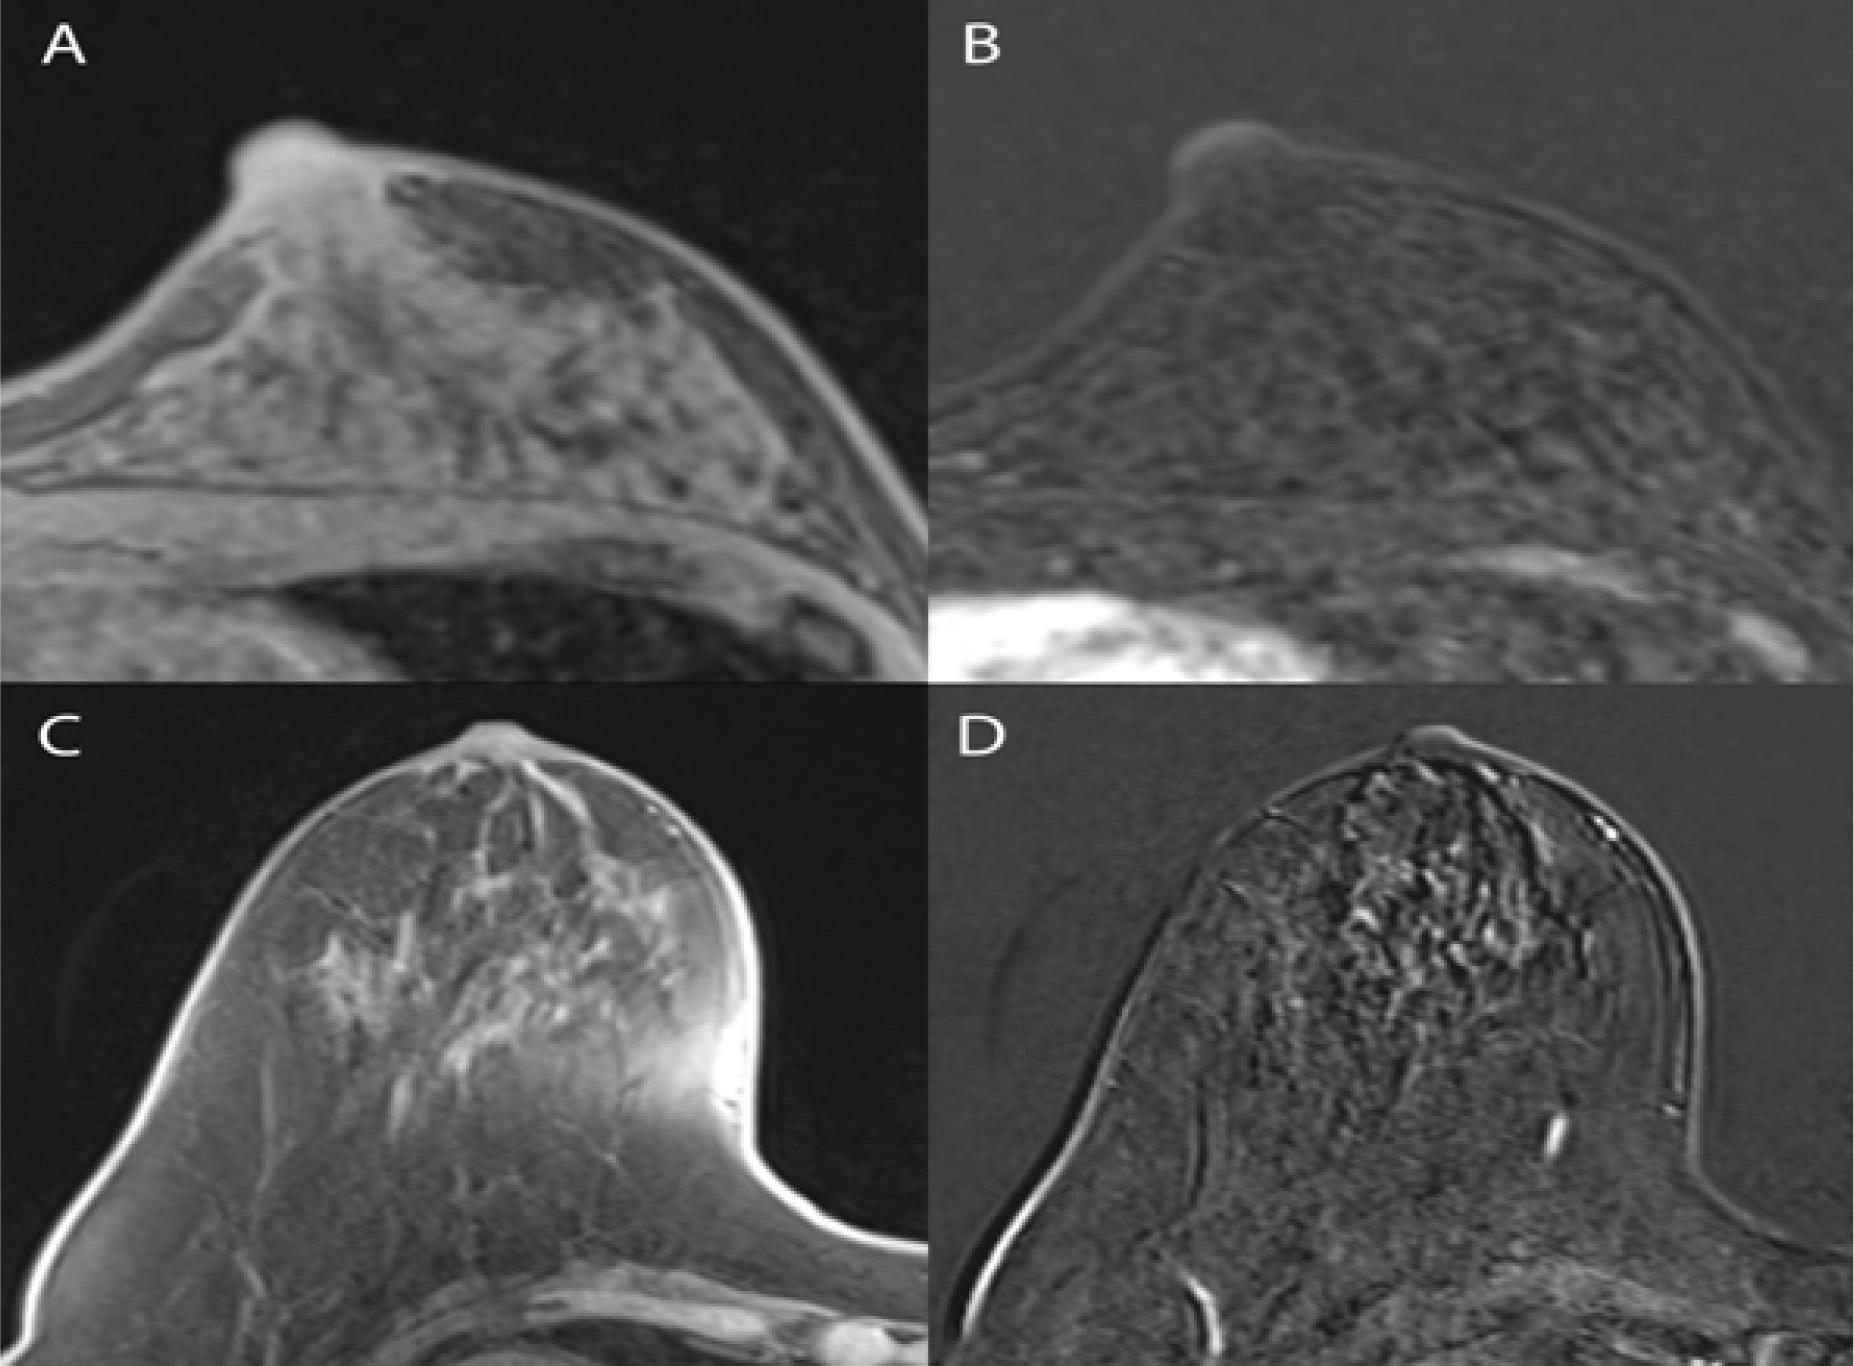

Figure 3